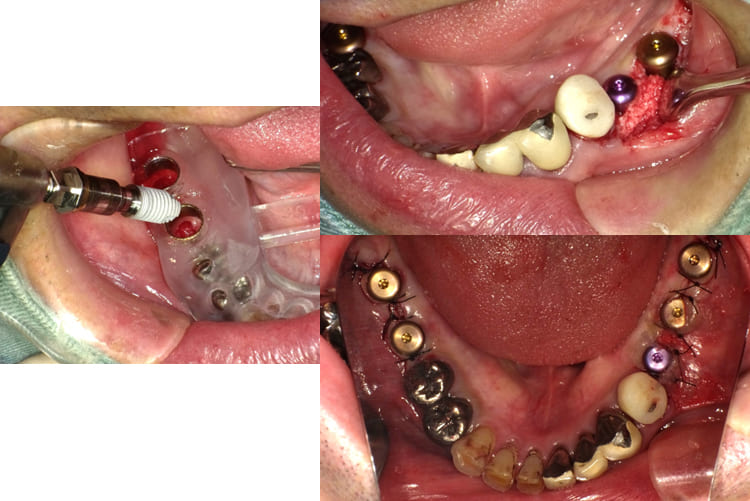

臼歯部のVertical Stopを確保した上で上顎前歯部のインプラント埋入手術を行った。

-

- 治療時の画像(出血などの症例画像あり)

上顎前歯部インプラント埋入を行った後3ヶ月で前歯部のインプラントの歯の部分を装着するための印象、咬合採得と温存できた#13,12,21への歯冠補綴を行った(歯科技工士さん立ち会い)。